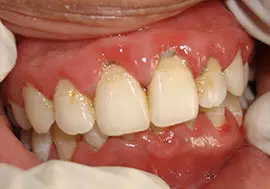

Some symptoms of periodontitis includes bleeding gums, bad breath, increased sensitivity to heat & cold and in later stages pain, swelling, pus discharge & mobility of teeth.

bad breath, and a persistent metallic taste in the mouth

Deep pockets between the teeth and the gums

Loose teeth, in the later stages